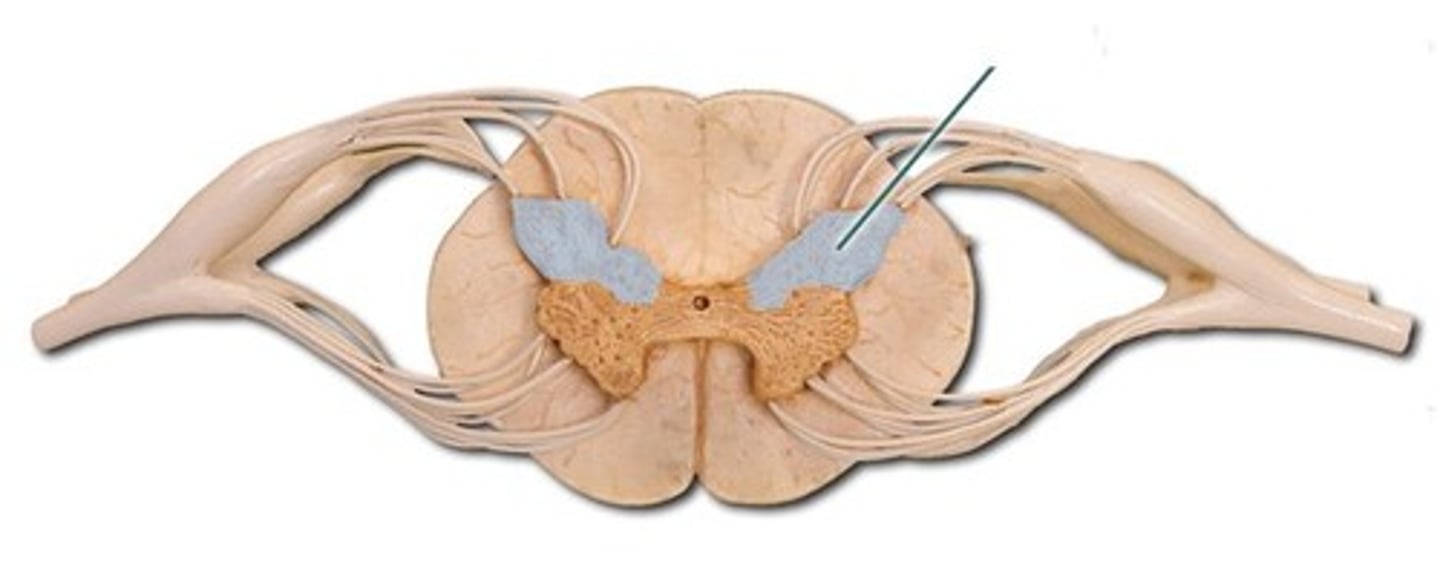

spinal cord

a major part of the central nervous system which conducts sensory and motor nerve impulses to and from the brain; housed within the vertebral canal

posterior (dorsal) rootlets

merge to form a root

posterior (dorsal) root

contains sensory axons

posterior (dorsal) root ganglion

contains cell bodies of sensory neurons

true spinal nerve

anterior root

contains motor axons

spinal meninges

dura mater, arachnoid mater, pia mater (PAD to protect the spinal cord from deep to superficial)

dura mater (spinal cord)

thick, outermost layer of the meninges; 5 on image

arachnoid mater (spinal cord)

middle weblike layer of the meninges; 4 on image

pia mater (spinal cord)

thin, delicate inner membrane of the meninges; 3 on image

central canal of spinal cord

center of spinal cord which contains cerebrospinal fluid

posterior median sulcus

a shallow vertical groove dividing the spinal cord throughout its whole length in the midline posteriorly.

anterior median fissure

a groove along the anterior midline of the spinal cord that incompletely divides it into symmetrical halves

gray matter of the spinal cord

cell bodies, dendrites, and unmyelinated axons arranges in a butterfly shape with anterior and posterior "horns"

posterior (dorsal) horns

contain axons of sensory neurons and cell bodies (sensory nuclei) of interneurons